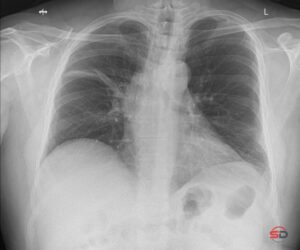

Atelektase im Thoraxröntgen

Im konventionellen Thoraxröntgen zeigen sich Atelektasen je nach Lokalisation sehr unterschiedlich. Ein Oberlappenkollaps kann sich als keilförmige Verdichtung mit Aufwärtsverlagerung der Fissur präsentieren, während basale Plattenatelektasen als horizontale oder schräge, bandförmige Verschattungen sichtbar werden.

Wichtig ist die systematische Beurteilung: Verlauf der Lappenspalten, Stellung des Hilus, Mediastinum, Zwerchfellkuppe und Rippenabstände sollten konsequent verglichen werden. Auch eine schlechte Inspiration kann den Eindruck einer Atelektase vortäuschen und muss erkannt werden.